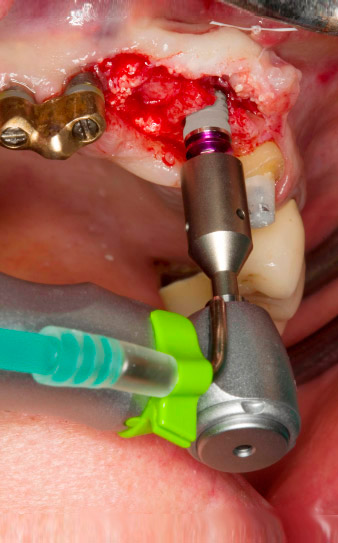

След първичното оздравяване, меките тъкани са оформени посредством базално разположения мост. Два месеца по-късно, обработваното поле е изложено на палатинална алвеоларна инцизия (Фиг 2). Размерите на алвеоларната кост са достатъчни в позиция 22. Фигури 2 и 4 показват препарацията на имплантното ложе, нарязващия винт и имплатирането, използвайки Implantmed.

Новият имплантологичен мотор е използван с подходящите обратни наконечници на W&H.